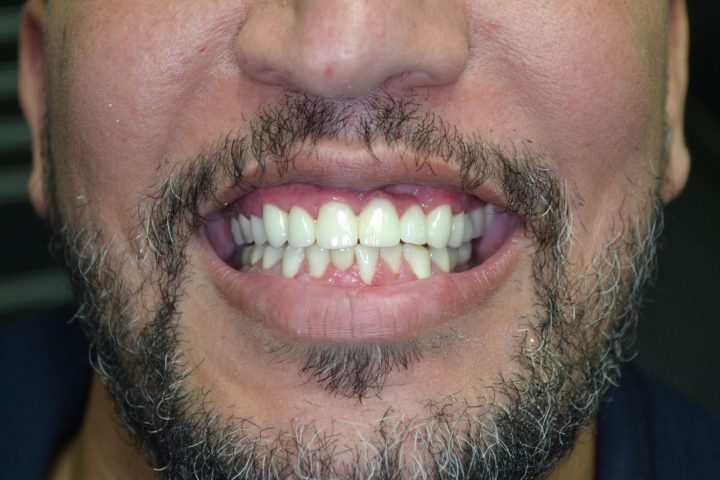

Mark

Mark ist ein englischer Patient bei uns, der sich in seinem ganzen Leben nach weißen Zähnen gesehnt hat. Sein Fall ist unregelmäßig, weil er früher eine andere ungarische Zahnklinik besucht, hat, wo er Implantate bekommen hat. Aber er war mit der Patientbetreuung nicht zufrieden.

Auf den Rat von seinem Freund hat er so entschieden, dass er die Behandlung in der Zahnklinik Centrocc Dental beenden möchte. Er hat diese Entscheidung nicht bereut, und hat die Klinik seinen alten Traum verwirklicht.

Auf seine Implantate haben wir durch Frau Dr. Erdélyi insgesamt 24 Stück Metallkremaik Kronen bearbeitet.